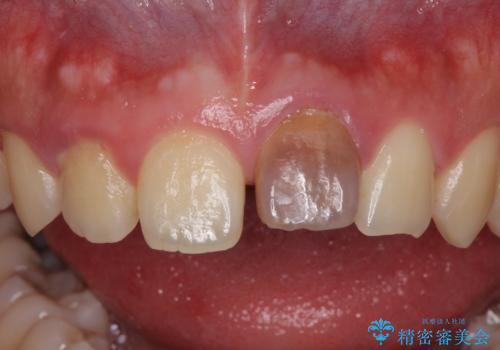

- 中学生の時にぶつけて以来、そのままにしていたところ前歯が変色してきたとのことで来院された患者様です。

レントゲン写真より、歯の中の神経組織が失活していることが分かったため、根管治療、ファイバーコアによる土台築製を行い、オーダーメイドタイプのオールセラミッククラウンにて補綴することとしました。